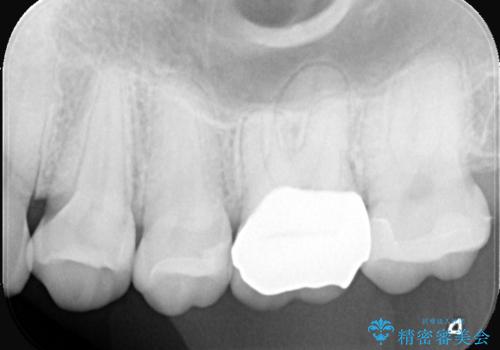

2回で完了した奥歯のセラミック修復

- 奥歯の虫歯治療を主訴にご来院されました。患者様から「できるだけ通院回数を少なく、早く治療を終わらせたい」というご要望があったため、短期間での完了を目指し、セラミックインレー(詰め物)とセラミッククラウン(被せ物)を併用する治療計画を立案しました。治療は精密機器を活用し、2回の来院で最終的なセラミック修復物を装着することを目指します。

今回の治療では、虫歯の大きさや深さに応じて、異なるセラミック修復法を適用しました。

比較的軽度な虫歯には、セラミックインレー(詰め物)で対応し、健全な歯質を最大限に残しました。

進行した虫歯や歯の強度が低下している歯には、セラミッククラウン(被せ物)を選択し、歯全体を保護することで破折を防ぎました。

短期間での治療を可能にしつつ、天然歯と見分けがつかない審美性と、長期的に安定する機能性を兼ね備えたセラミック修復を実現しました。